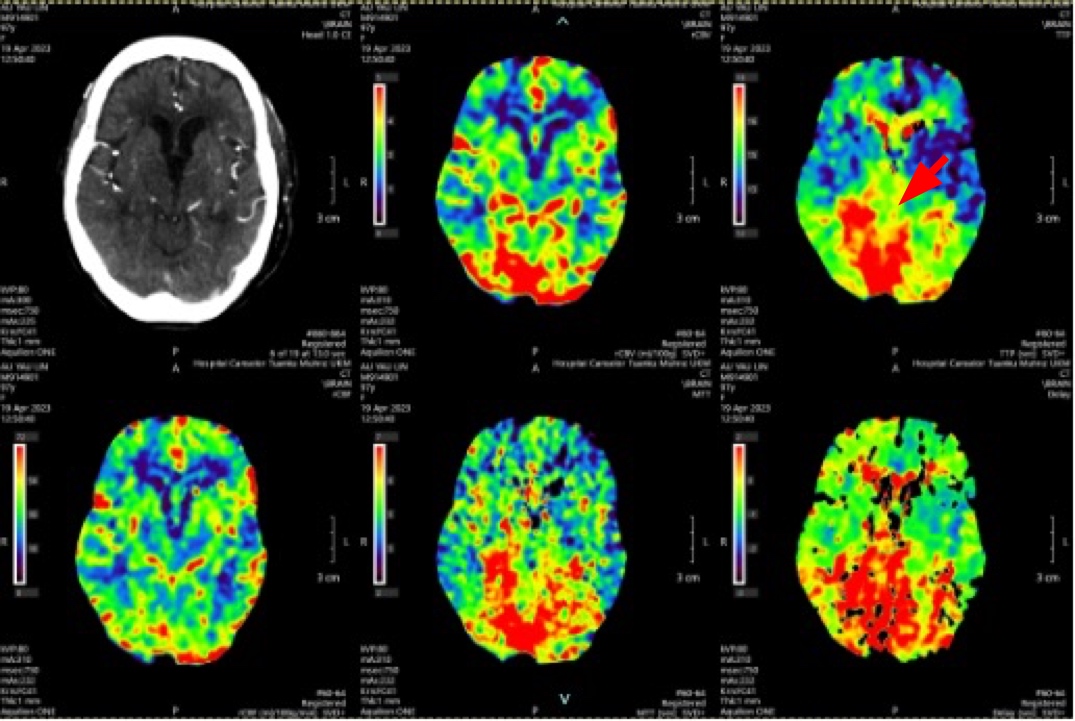

A delay in recognising acute posterior circulation infarct (POCI) can cause a delay in treatment and high mortality rate. There has been an increasing trend in incidence of stroke among the elderly. Treating acute stroke in elderly has been challenging due to the lack of data on the functional outcome and mortality risk. A 97-year-old woman had left sided weakness upon waking up from sleep and dizziness two days prior. Upon arrival, her Glasgow Coma Scale (GCS) was E3V4M6, BP 162/112 mmHg, NIHSS score 10, left sided power 3/5 and right sided power 4/5. Her computed tomography (CT) angiography brain showed P2 segment of right posterior cerebral artery and distal basilar artery thrombosis, with a posterior circulation territory mismatch. Thrombolysis was given immediately. She was discharged with NIHSS 5, GCS E4V5M6 and power bilateral limbs 4/5. She was put on lifelong Apixaban for stroke prevention and underwent post-stroke rehabilitation. The time of occlusion was decided based on the time a patient was last seen well. Studies have shown that patients aged 80 years and above presenting within 3-4.5 hours from symptoms, perform well with both intravenous thrombolysis and thrombectomy, with no increased risk for intracranial hemorrhage and death.